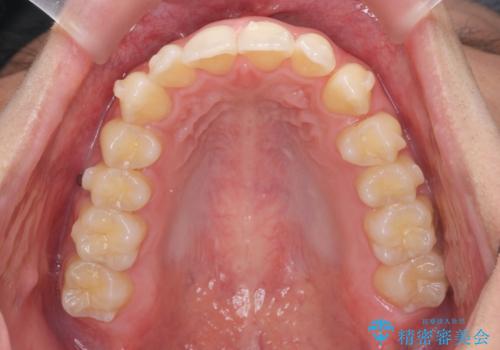

過蓋咬合・上顎前突・叢生を改善するマウスピース矯正

・前歯の深い噛み合わせ (過蓋咬合)

・上顎前突(Angle Class2)

・叢生(がたつき)

以上のような問題点をマウスピース矯正インビザラインとマイクロインプラントを用いて矯正治療を行い改善して行きます。

20時間以上のマウスピース装着、ゴムかけを遵守していただいたおかげでしっかりと噛み合わせ、がたつきの改善を行うことができました。